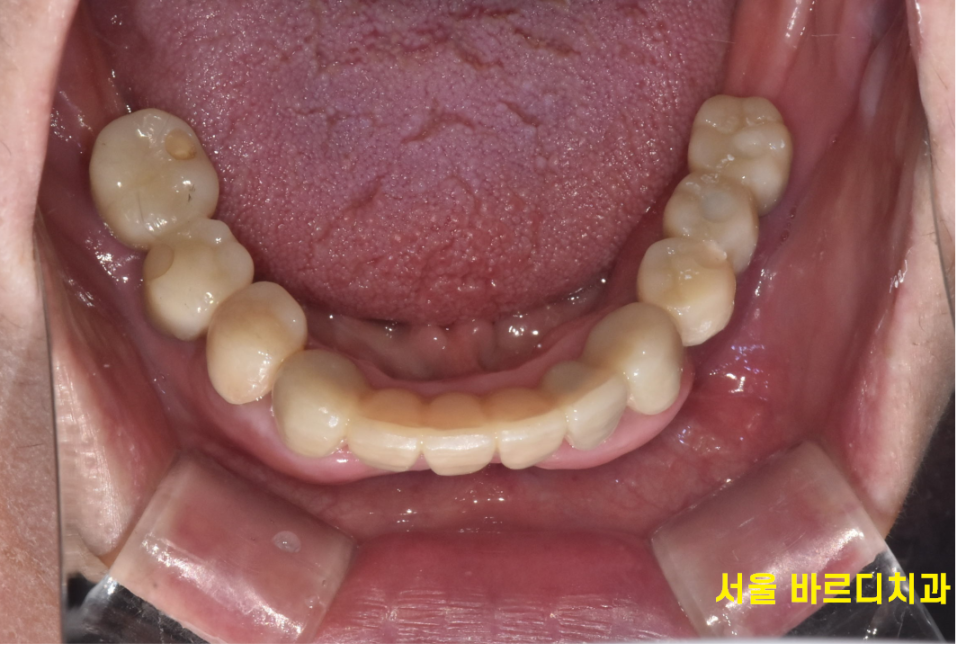

240430

13개의 임플란트 식립 후

전체적인 치아 치료 완료된 사진입니다.

맨 처음 상태가 기억나지 않을 정도이시죠~?

없던 치아가 생겨

씹는 느낌이 새롭다는 환자분 말씀이 기억납니다.